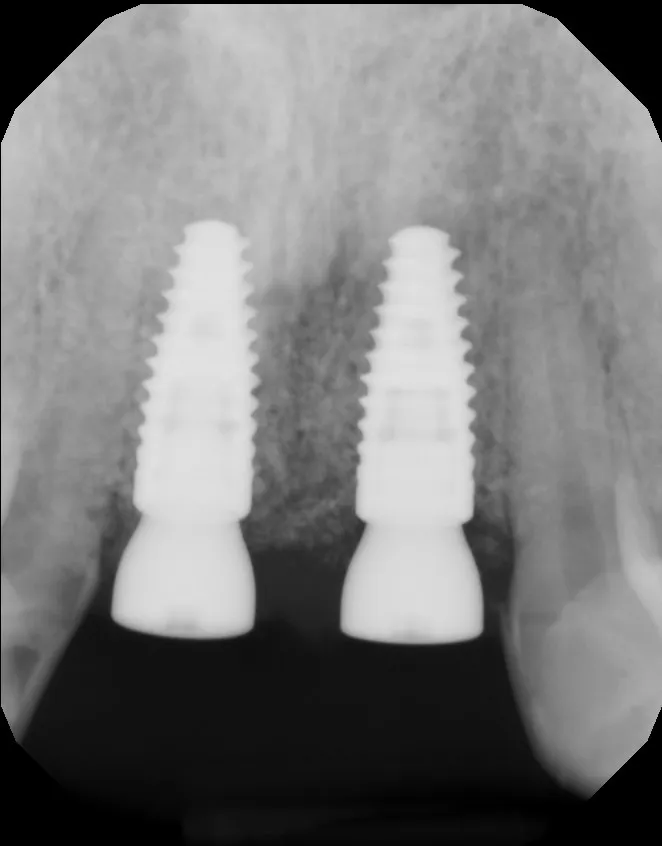

Xray of full mouth implants Vancouver BC